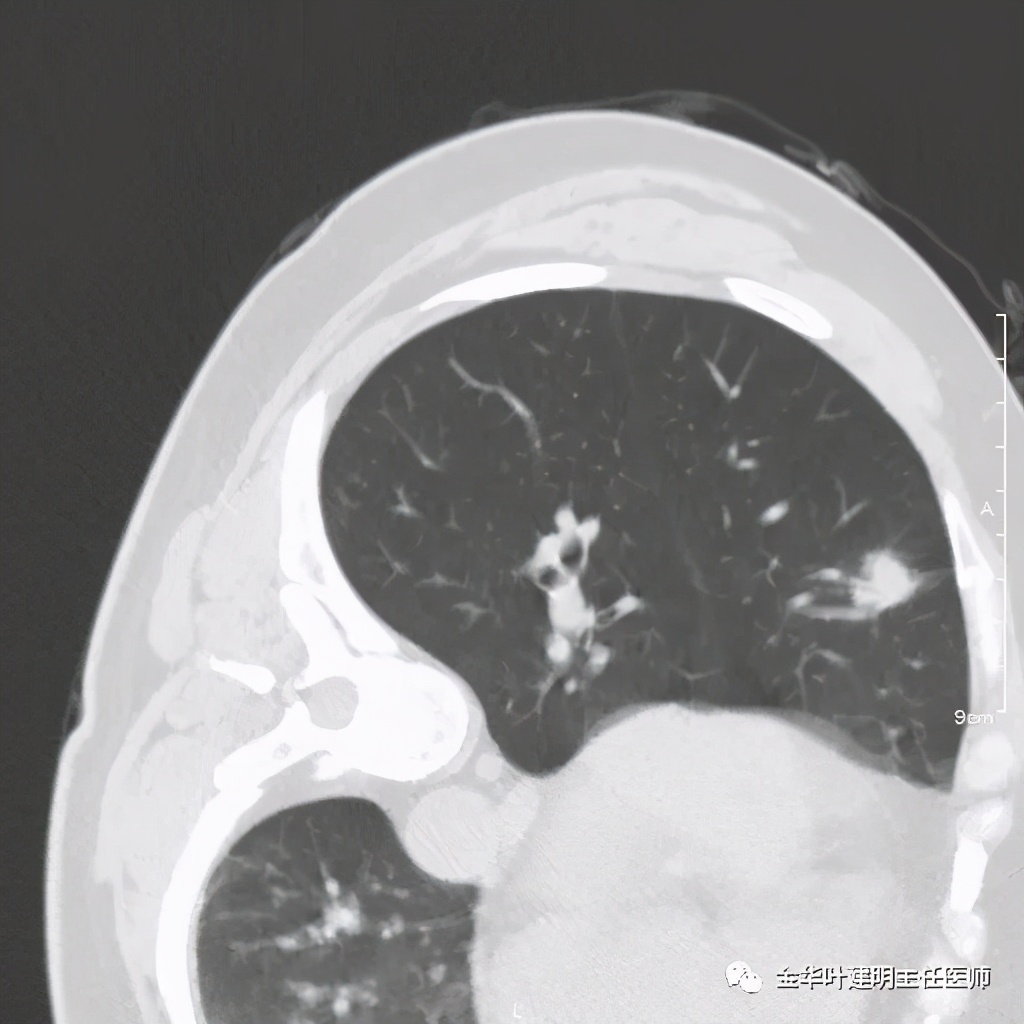

二、浸润性腺癌贴壁生长为主伴腺泡状生长型:

影像特征:与单纯贴壁型的区别是其 纯磨玻璃结节内部出现实性成分 ,但较少,密度高的部分密度不均匀,相对较散在,再加上瘤肺边界清楚、细毛刺状边缘、血管进入、整体轮廓较为清晰。上图绿色箭头示血管、紫色示边缘锯齿状。此型一般与原位腺癌或微浸润性腺癌交叉较少,有时慢性炎伴纤维增生可能会有类型改变,但纤维增生不容易在病灶中央,所以误诊较少,也相对容易与AIS与MIA区分,不典型增生不大有这种表现的。